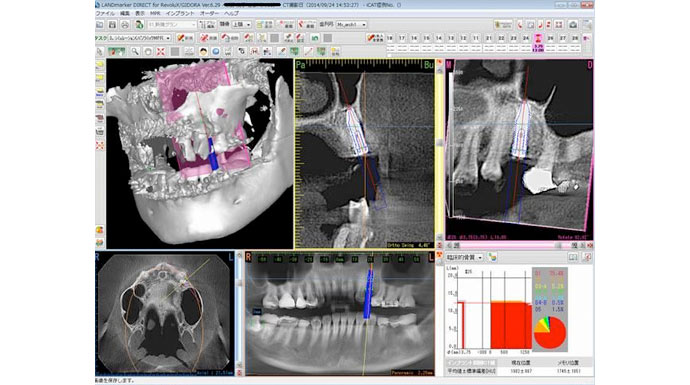

当院はCTを完備しています。こちらはCTシミュレーションソフトの画像です。難しいケースでは術中にもCT撮影を行い、位置や方向を確認しながら施術を進められるので、インプラントを精密に埋め入れることが可能です。安全が最優先なので、これで失敗や事故などを防ぐことができます。

また、シミュレーションを行った方の個人データからインプラントガイドという道具を作った場合は、CT撮影をせずに精密なインプラント治療を行えます(上記のCT画像は、シミュレーションした部位と実際にインプラントを行った後の比較をするためのものです。インプラントの埋め入れ位置や方向、計測したサイズまで精密に行えています)。